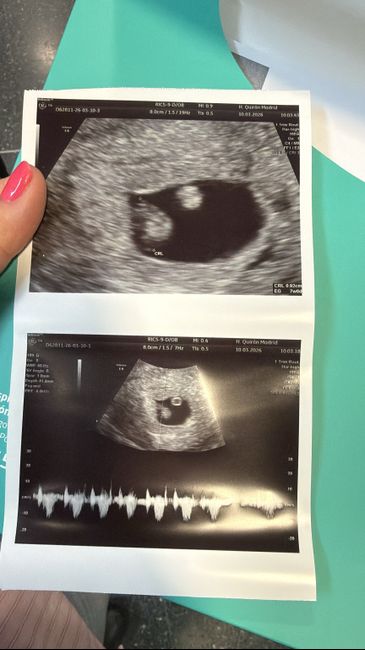

Hola chicas, mi bebé arcoiris… mi eco de hoy via vaginal. En verdad me da igual el sexo, solo quiero que venga san@ pero me da curiosidad el metodo jejej

Hola! Me ayudáis por favor? Niño o niña? Es una eco en papel. Gracias!!!Método Ramzi 5